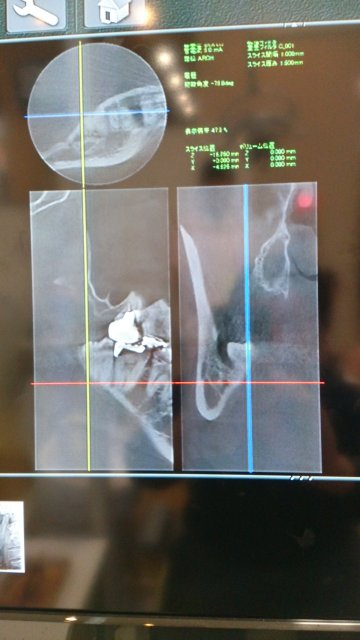

201605101516542861 抜く前にCTスキャナーで神経と動脈と親知らずの位置を調べて

Dsc_28591 安全性を確認だぉ。

CT右下の画像。